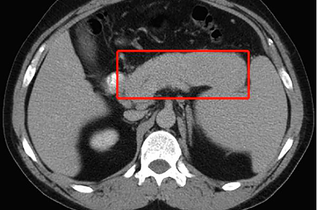

[最佳答案] IgG4相关疾病是一种自身免疫病。这种病主要是由于炎性纤维化,可以造成多个器官和系统的器官肿大组织破坏,甚至是器官功能衰竭。由于这种疾病血清当中的IgG4水平升高,所以以此命名。这类疾病通常会有1个或多个器官肿大。病理学会显示有淋巴细胞和浆细胞的浸润以及纤维化。治疗上以激素治疗为主,同时可以加用免疫抑制剂,比如硫唑嘌呤,吗替麦考酚酯,环磷酰胺等等。